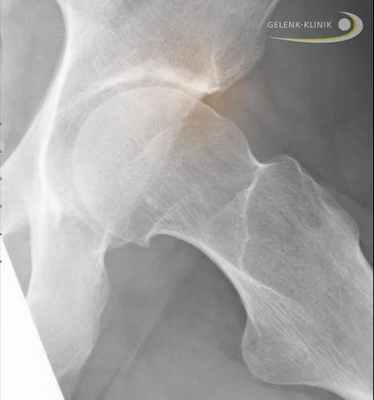

Подтвердить диагноз болезни Пертеса помогает рентгенография ТБС. Как правило, в ходе лечения, которое может занимать до двух лет и более, ребенку проводится несколько рентгенографических исследований. На фоне лечения наблюдается постепенное улучшение рентгенологической картины.

Болезнь Пертеса затрагивает левый тазобедренный сустав. Противоположный сустав в норме.